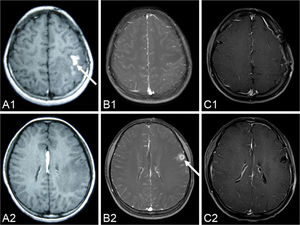

CASE DESCRIPTIONA fifteen-year-old girl suffered from facial and upper limb numbness on her right side one year ago. She was previously diagnosed with encephalitis at the Department of Neurology until she suffered a generalized tonic–clonic seizure six months later. MRI showed a contrast-enhanced lesion with an irregular shape located in the left frontal lobe (Figure 1 A1 and A2). The patient was advised to undergo further treatment in the Department of Neurosurgery. However, because the seizure was acutely controlled, she was noncompliant with treatment. One week before admission, the seizure became uncontrollable. An MRI revealed a contrast-enhanced lesion with an irregular shape (Figure 1 B1 and B2); however, local migration of the lesion was observed.

A series of pre-operational MR images demonstrates the local migration of an irregular, enhanced lesion (arrow) in the left hemisphere (A1-A2) six months before the operation; (B1-B2) three days before the operation. The lesion disappears in the post-operation MR images over the two-year follow-up period (C1-C2) 26 months after the operation.

The histology of the larval cestode showed a brush border and eosinophilic smooth muscle fibers (Figure 3A). Some portions of the parasite body contained calcareous bodies (Figure 3B). A new tunnel-like structure with infiltrating plasma cells and eosinophils was identified in the tissue (Figure 3C). Under higher power, calcareous bodies were also observed within the tunnel (Figure 3D). Based on the pathological findings, the patient history and serum test results, a final diagnosis of cerebral sparganosis was made. During a follow-up period of more than two years, the patient's symptoms disappeared. No enhanced lesion was found on MRI at 26 months after the operation (Figure 1 C1 and C2).